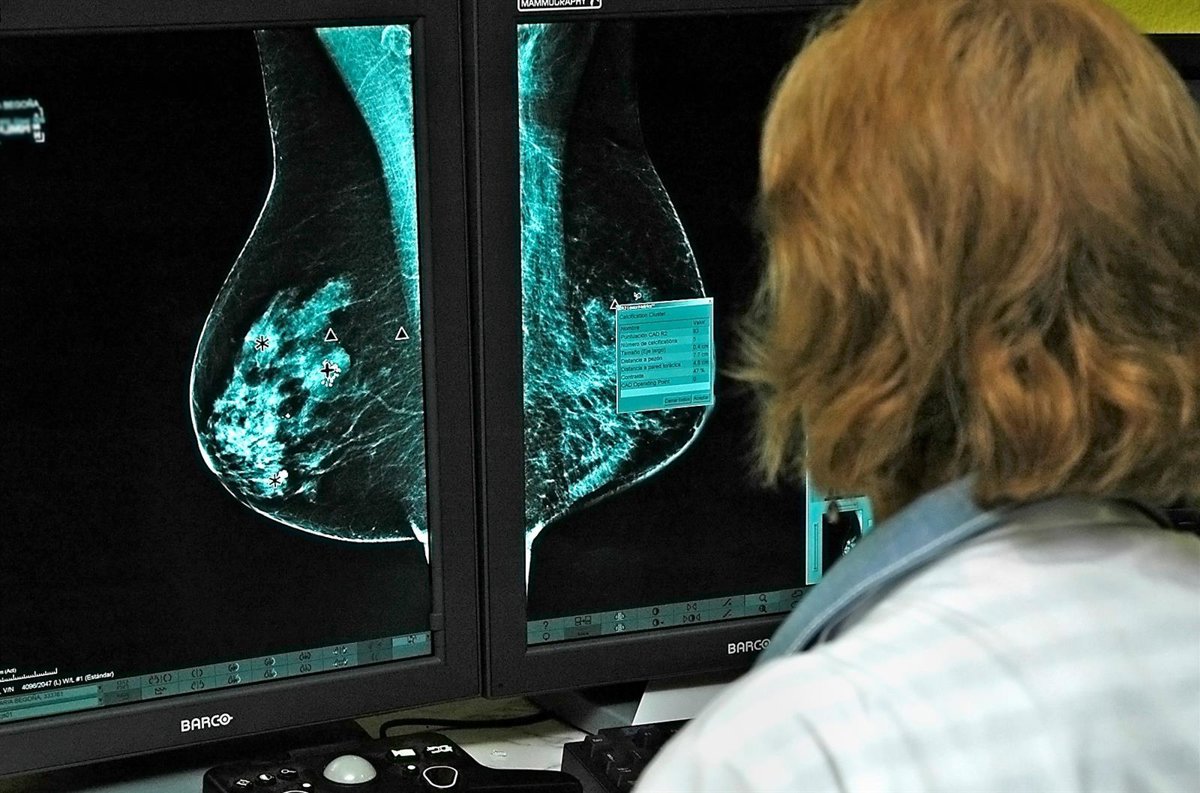

Archivo - Mamografía.

Archivo - Mamografía. - JCCM/EUROPA PRESS - Archivo